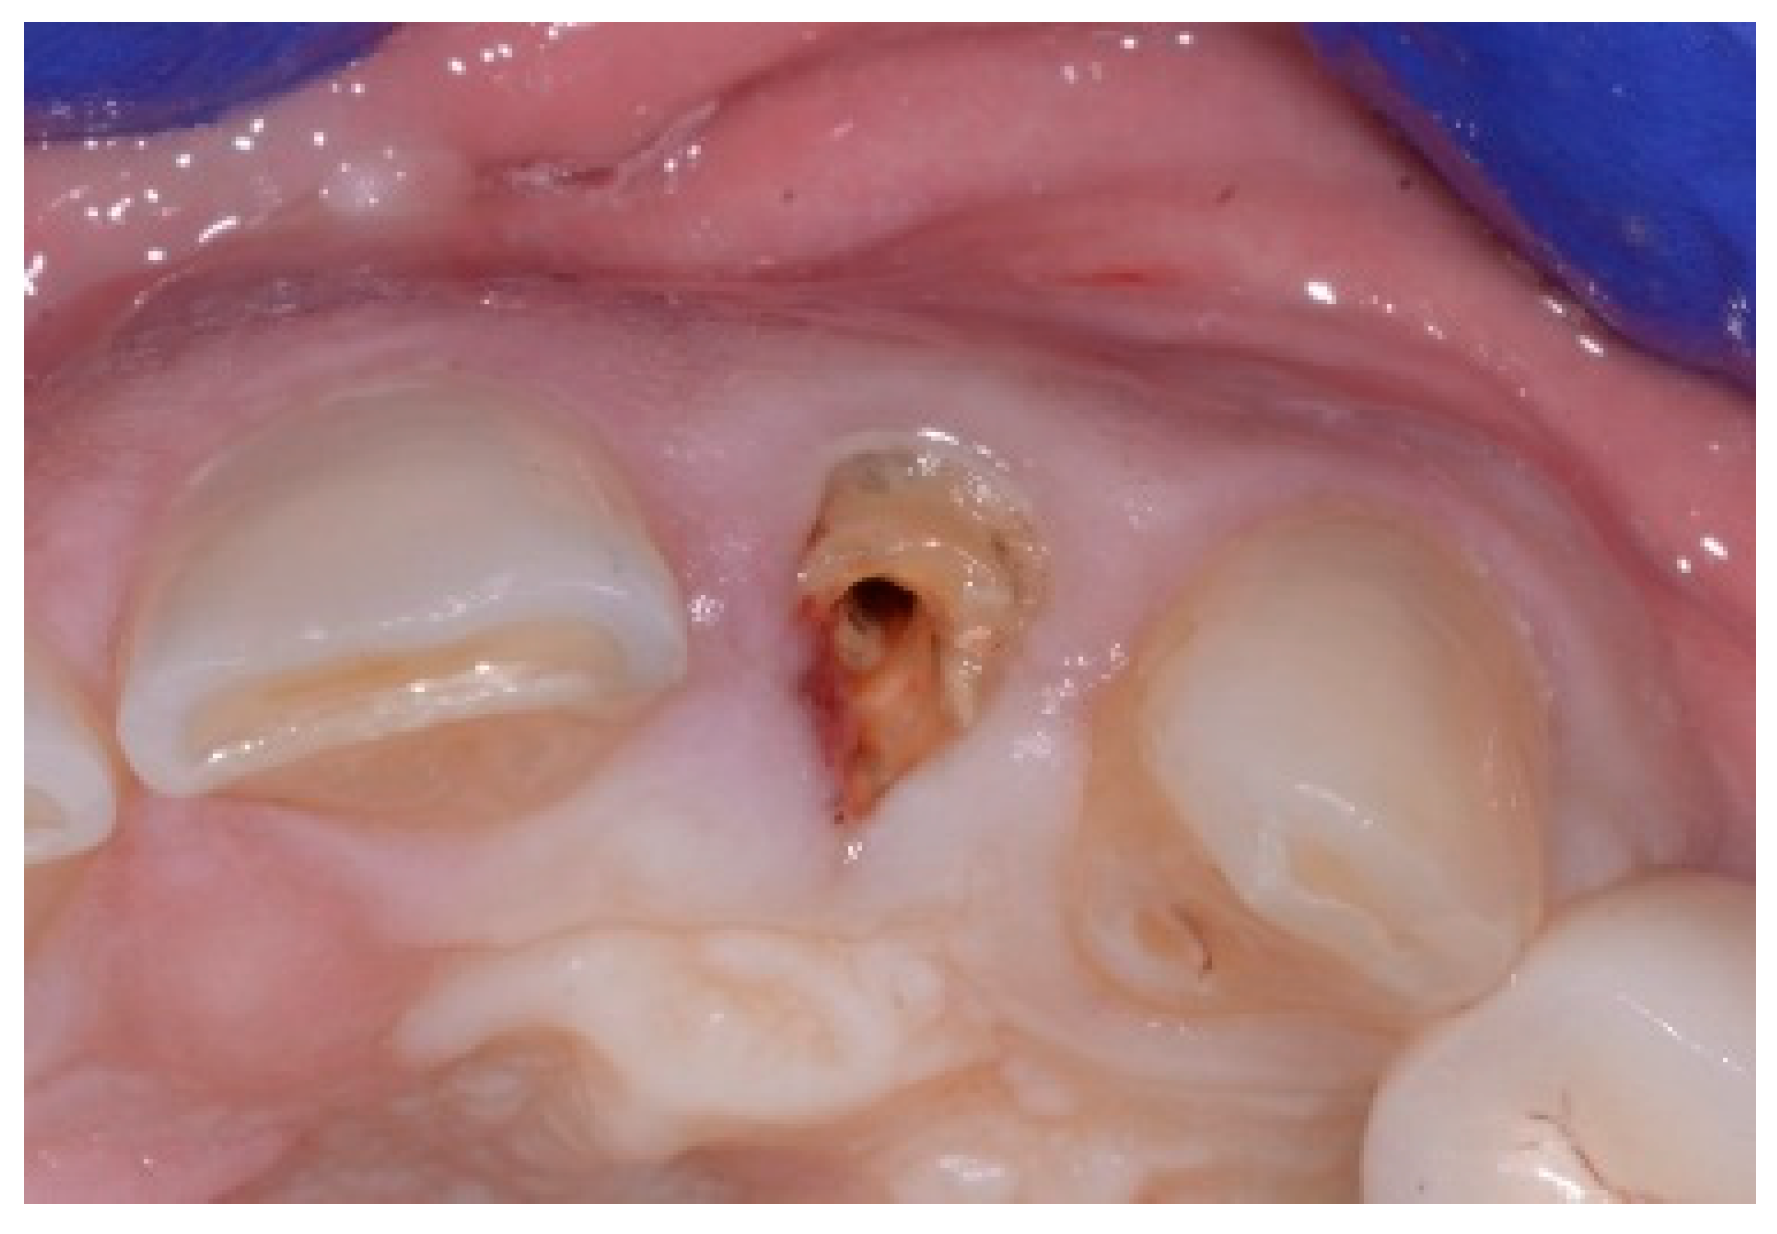

Figure 13.

Clinical view of extraction site (note tissue above tooth #9).

A 50-year-old female in good health and a non-smoker presented to our clinic with a failing maxillary left central incisor (Figure 13). The treatment plan consisted of the extraction of the existing tooth and replacing it with an implant. The preoperative surgical protocol described in patient 1 was followed. An L-shaped aesthetic flap design was used, revealing a buccal wall defect (Figure 14). The implant was placed with a screw-retained chair-side temporary crown (Figure 15), followed by the placement of bone graft material over the boney defect (Figure 16). A double-layer collagen membrane was placed and the flap closed. After six months, the final ceramic crown was inserted (Figure 17).